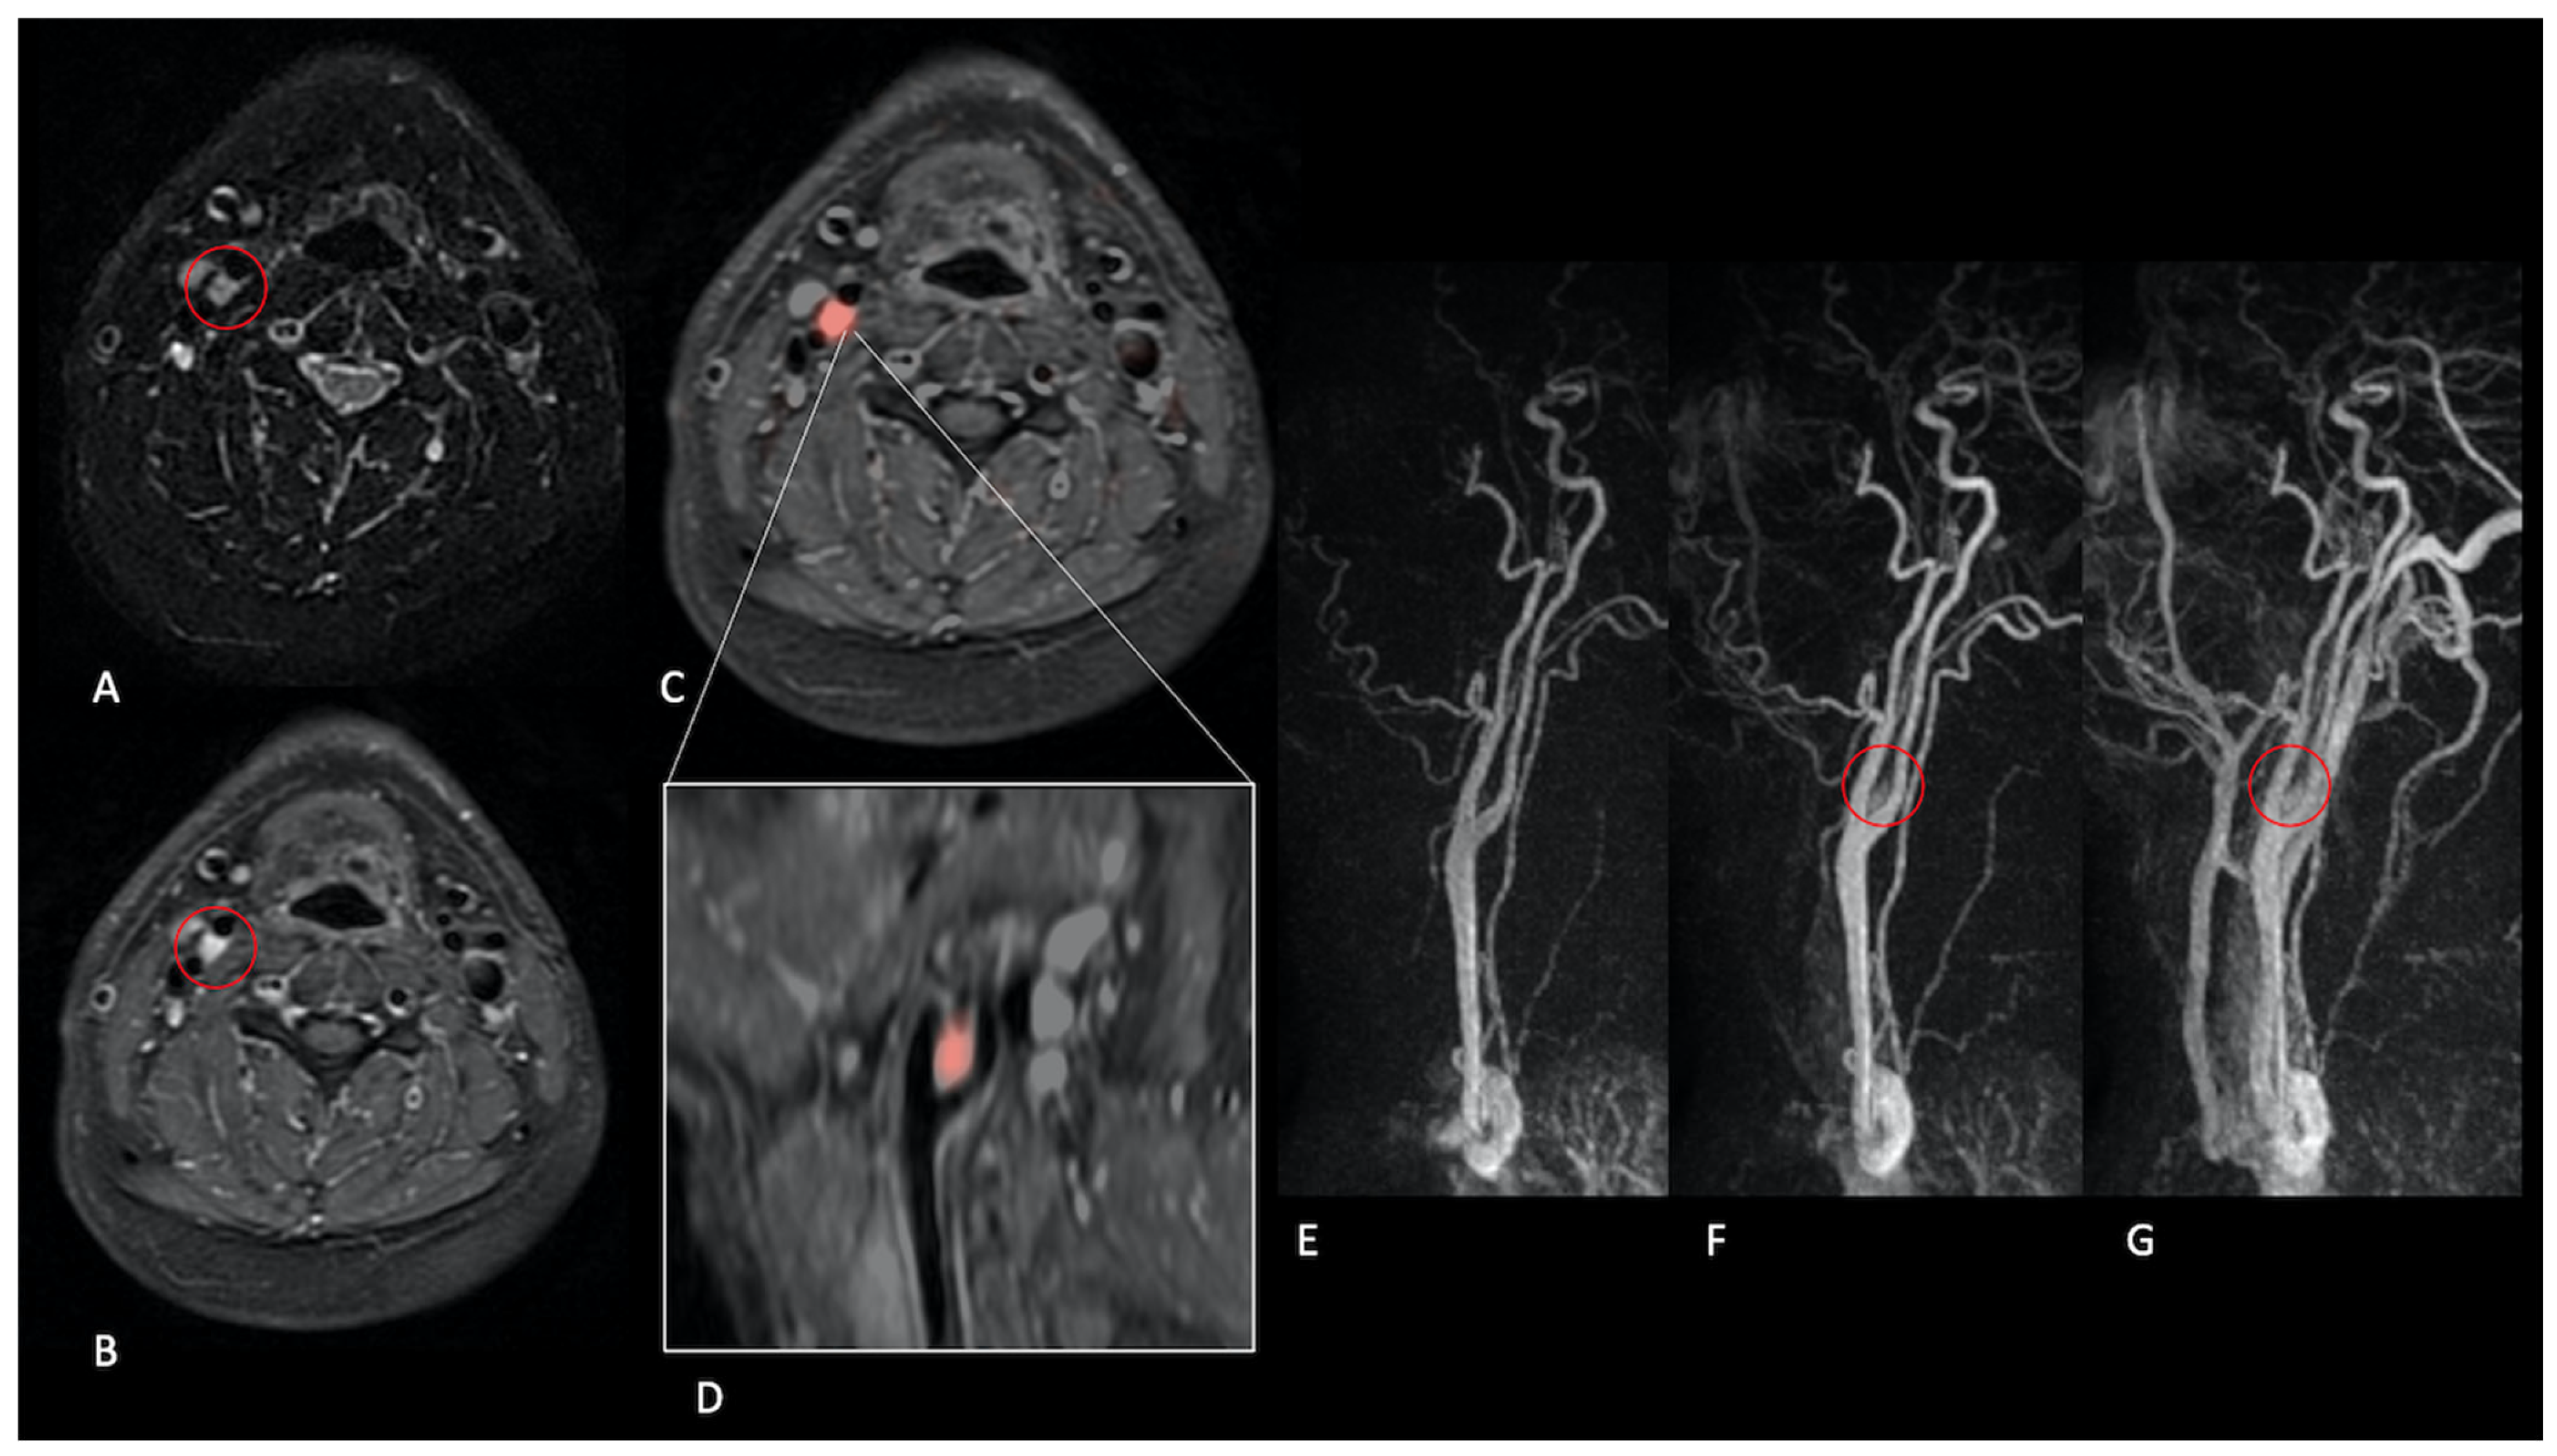

- Presence (present | indeterminate | absent) and site of a lesion.

- Sequence(s) providing greatest diagnostic confidence in detecting/localising NPGLs:

- Single sequences—FS-T2, CE-FS-T1, pcASL, and TRICKS;

- Combined sequences—FS-T2 + CE-FS-T1, and pcASL + TRICKS.